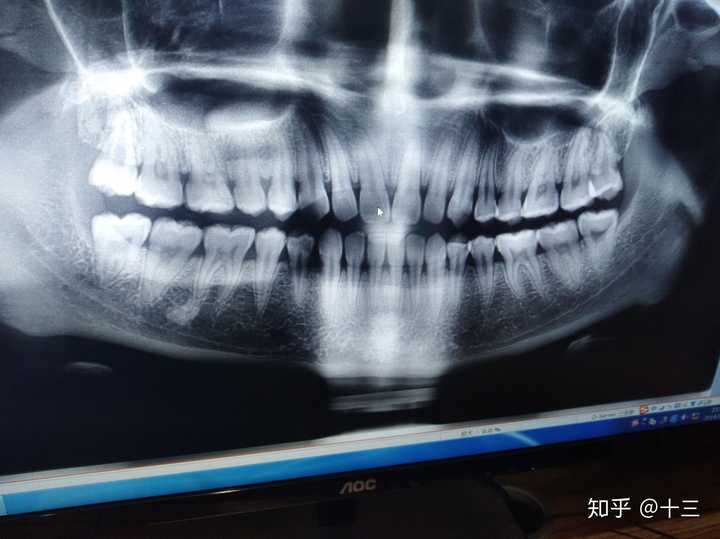

正常智齿片子

正常智齿片子,智齿片子

拍了片子请问需不需要拔掉智齿呢

沙师妹只好先跑去医院 到医院 医生喊我先拍片 一看片子长了4颗智齿

智齿片子

智齿x光片